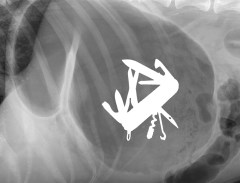

Radiologie en Urgence: Guide de Survie – Colloque de l’AMVQ – Offert en salle à Laval et webdiffusion simultanée – Dimanche 16 mars